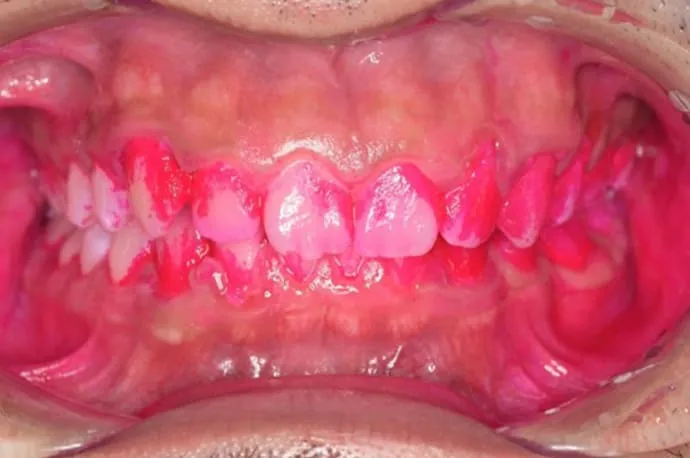

歯磨き指導例

治療前

治療後

こちらの画像は、ブラッシング前後の染め出しの画像です。汚れがついている部位は濃くピンクに染まります。1回の歯磨き指導でも、汚れの付着が大きく減っていることが確認できます。ぜひ一度、高輪の歯医者「TAKANAWA GATEWAY Clinics 歯科・矯正歯科」へご来院いただき、自己流の歯磨きから卒業してみませんか?

症例タイトル 歯磨き指導・染め出しの症例

主訴 歯科検診をしてほしい

治療内容 歯磨き指導・染め出し

治療期間 1日

治療費 保険診療 歯磨き指導300円

その他歯石取りなどの金額が追加

メリット ・口臭や口の中の汚れの軽減

・歯茎の出血や腫れがなくなる

・虫歯のリスクが減る

リスク・副作用 ・汚れ染め出しの液を使うと、一時的に歯の周辺にピンクの色がつく(汚れが落ちればなくなる)